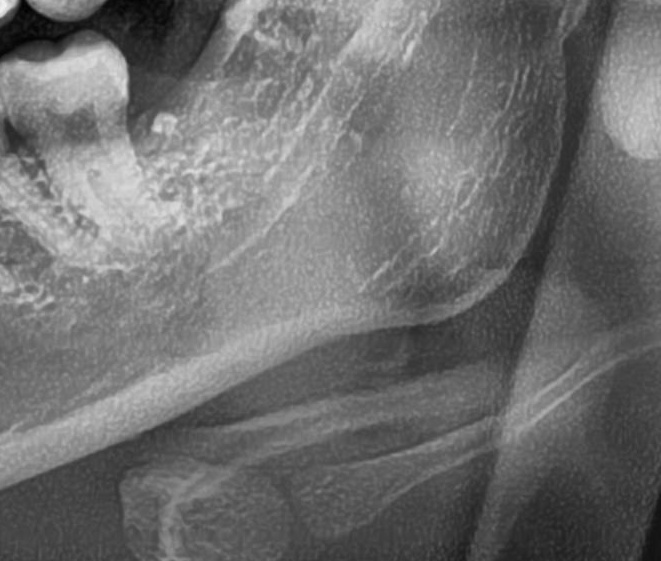

次にパノラマ写真を撮影してみると、左下の親知らずは手前の歯を押すように斜めに生えているのが確認できました。

さらに、下顎の親知らずは下歯槽神経に非常に近いところに生えている場合もあるため、CTも撮影し詳しい解析を行います。

親知らずが生えている位置が、神経に近い、あるいは神経に当たっている場合は、大きな病院に紹介する場合もあります。

親知らずの根っこは下歯槽神経から近い距離にありますが、抜歯は可能との診断でした。